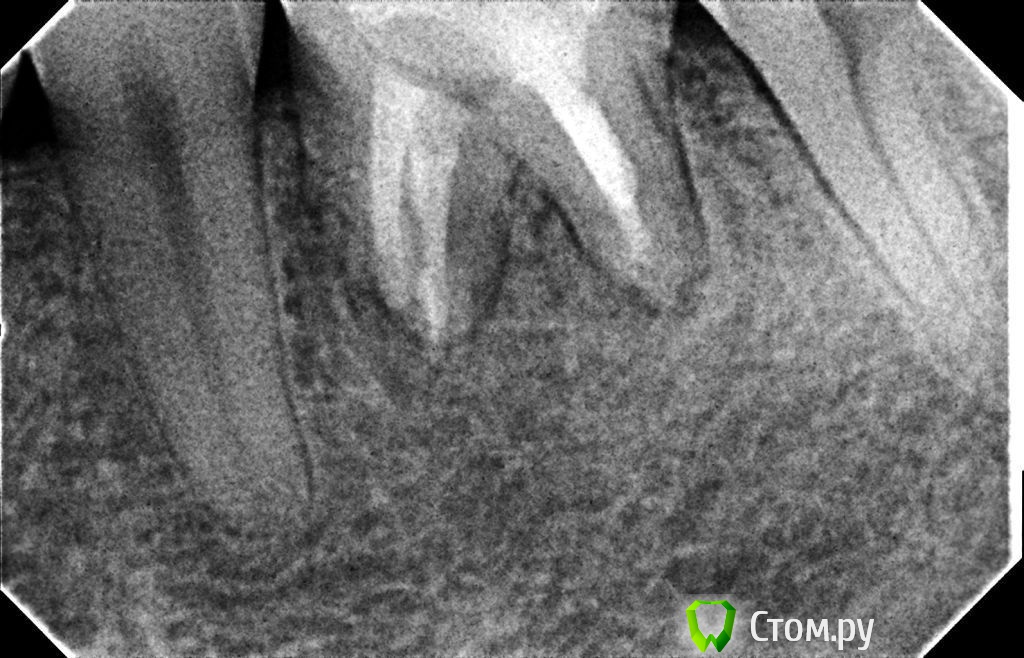

Hans85 Опубликовано 10 января, 2014 Автор Поделиться Опубликовано 10 января, 2014 (изменено) .Новый кейс-совсем свежий пока без долгосрочного результата.Пациентка попала случайно удаляла зуб 28 и хирург сделал ОПТГ,где стали видны обширные периапикальные процессы в области 37 47.Побывав у меня на консультации и услышав план лечения и стоимость,пациентка решила видимо полечить подешевле.,побывав на консультациях в нескольких клиниках и в итоге даже попала к главному стоматологу нашей области. Все ей сказали что удаление онли. Вернулась,-засада была в том что план я писал исходя из ОТПГ не сделав прицел(виноват),сделав прицел понимаю что все сложнее чем я думал-ну что же тем интереснее.Переписав план лечения и подняв ценник на 40%(пациентке не оставалась выбора),начали лечение.1-посещение-ревизия пломбы.понимаю что кто то до меня с маниакальным упорством пытался запломбировать мезиальный язычный канал каналонаполнителями. Убрал два фрагмента из верхней трети мезиального язычного.2-посещение еще фрагмент из мез язычного плюс немного с дистальными поработал(их оказалось два сплит в верхней трети)3-визит обошел фрагмент в мезиальном щечном и доработал остальные каналы.4-визит -паковка.На предпоследнем снимке видны поры-допаковал(просто на финальном не очень видно) Изменено 10 января, 2014 пользователем Hans85 Ссылка на комментарий